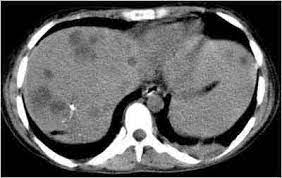

Epos

Epos from epos.myesr.org. Para más información pulse aquí para ir al website.